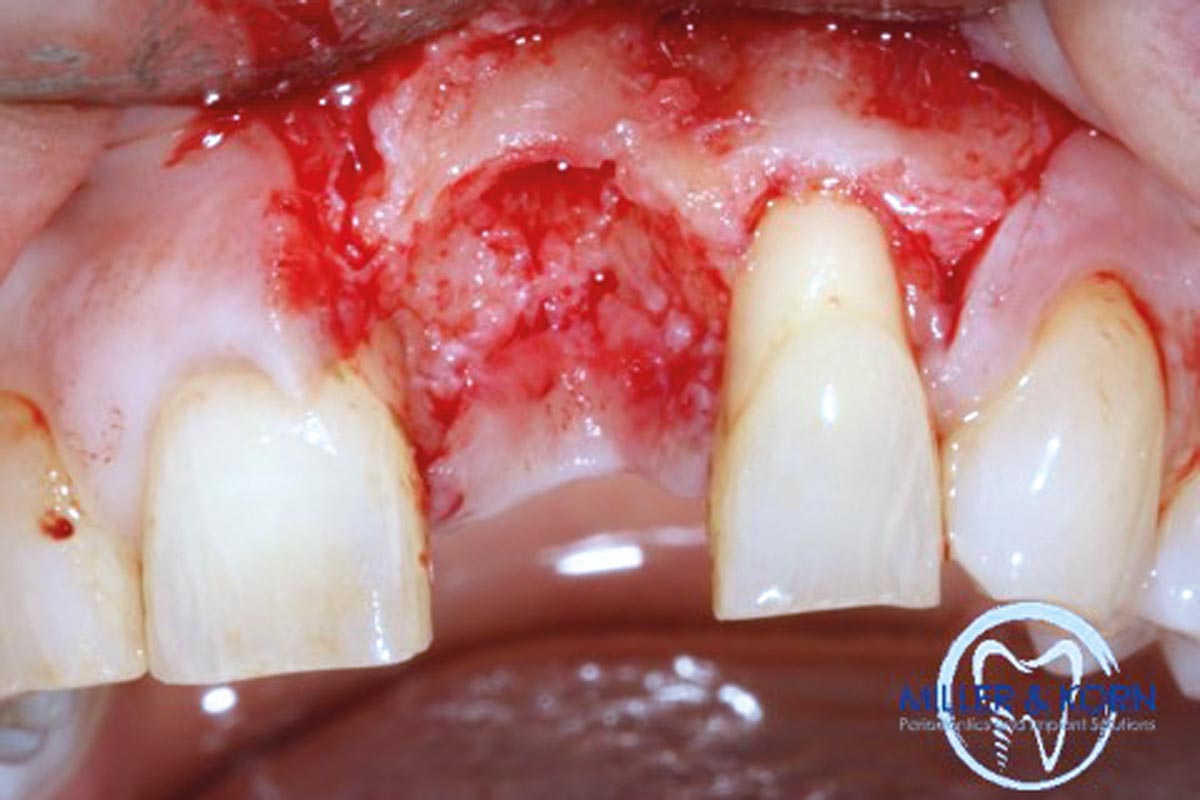

05/39 - Occlusal view of the extraction siteImmediate implant placement and correction of horizontal and vertical bone loss using an allograft bone ring, cerabone® and Jason® membrane - Drs. Miller and Korn